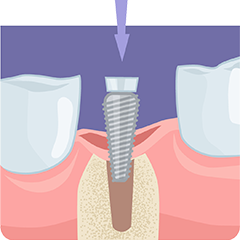

インプラント

歯槽骨に埋め込むチタン製の人工歯根です。骨との結合(オッセオインテグレーション)を促進する構造を持ち、インプラントの土台となります。

歯を失った箇所の歯槽骨にドリルで穴を開けます。

インプラントを埋め込み、歯ぐきで覆って縫合します。しっかりと固定されるまで数か月間待ちます。

再度歯ぐきを切開し、人工歯を取り付けるための部品(アバットメント)をインプラントの上部に装着します。